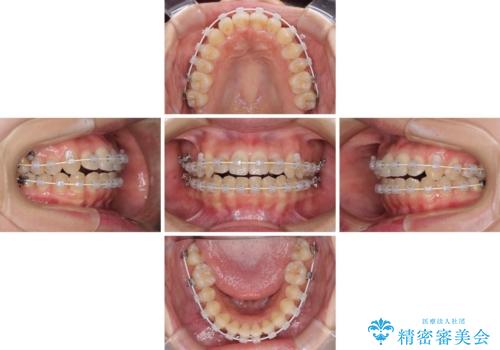

- 前歯のデコボコを気にして来院された患者様です。

上顎右側犬歯が八重歯になっており、それによって奥歯が前方に移動しているため、右側の咬み合わせの改善が必要と判断されました。

マウスピース矯正では改善に時間がかかる、あるいは改善しきれない可能性があることを伝えたところ、短期間で確実に治療ができるワイヤー矯正を選択されました。

より治療を速やかに行うため、上顎右側にアンカースクリューを使用し、目標としていた1年半ほどで治療を終えることができました。